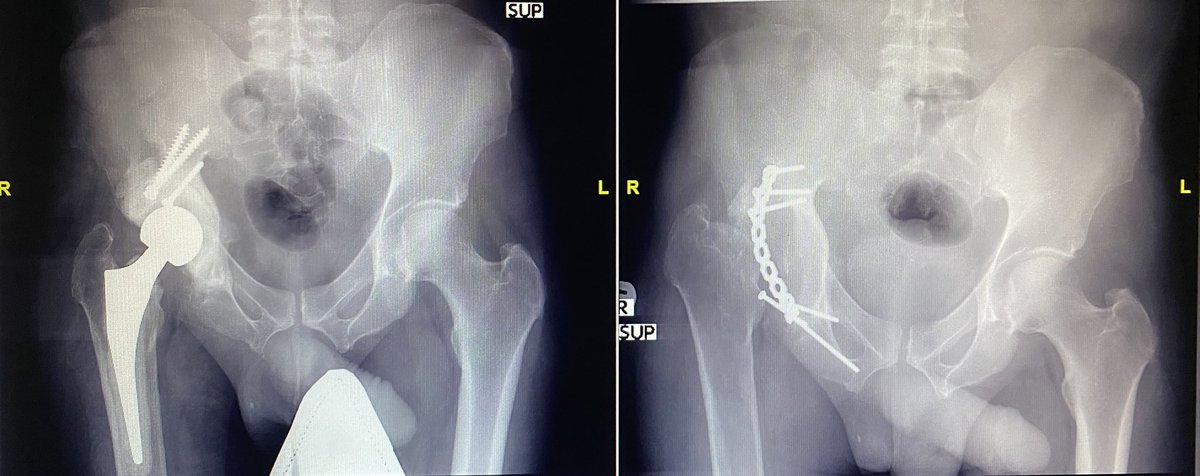

مريض أربعيني، أصيب بكسر الجوف الحقي، تعطل عن مصالحه خمس سنوات، زار عيادتي و هو في وضع يندى له الجبين...

⛔️فشل تثبيت كسر🙁

⛔️تلاشي في عظم رأس الفخذ☹️

⛔️التهاب جرثومي😢